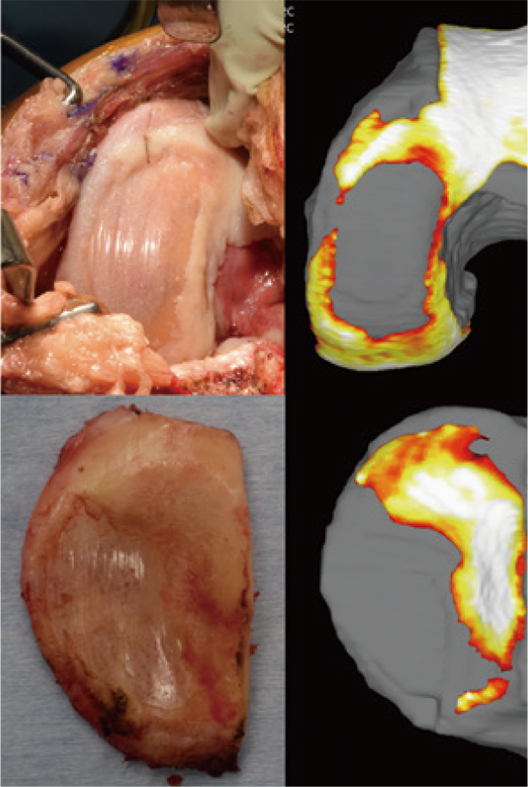

膝関節解析で構築した3D像と実際の関節面は、どの程度相関しているのだろう。再生医療施行後、人工膝関節置換術を希望され、術中直視下で関節面を評価できた症例を提示する。症例A(図5)では軟骨欠損部の境界は多少の誤差があるが、全体像をよくとらえていることがわかる。しかし、症例B(図6)では我々の視覚的認識と膝関節解析の判定に誤差があるようにも感じる。膝関節解析は軟骨の有無を信号値などのさまざまな特長量から判断し、厚みとして表現しているが、我々の視覚は軟骨の有無を色調や質感で判断しているため誤差が生じるものと考えている。このため、症例Bでは膝関節解析では1mm未満でも軟骨があれば色調の変化で表現した部位が、我々の視覚ではわずかに残っているだけの強い変性をともなった軟骨であるために軟骨欠損のように見えてしまう。これを考慮すると膝関節解析で描出された膝と直視下の膝では、それぞれの診断に若干の差異がある可能性も考えられる。一方で、変形性膝関節症で多く見られる骨棘に伴ってできた軟骨様の組織は(矢印)、軟骨として識別されることはなく、精度の高さも窺えた。

図5:症例A 術中と3D-MRIの違い

図6:症例B 術中と3D-MRIの違い